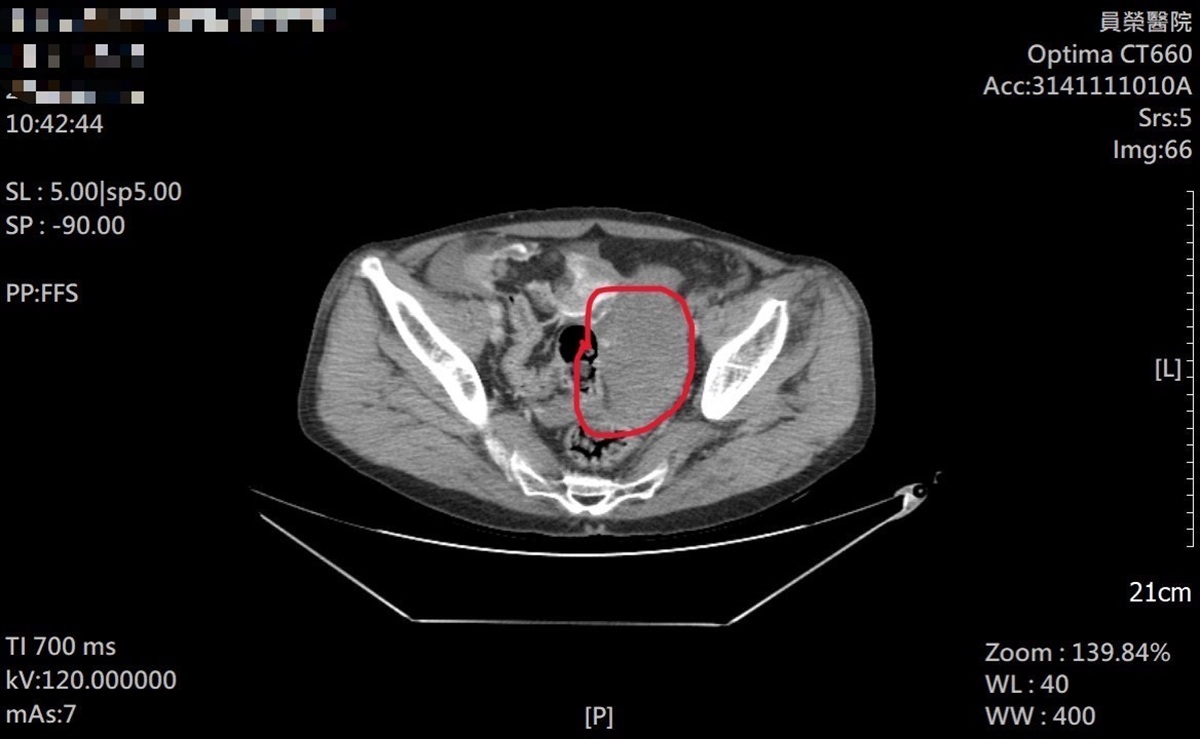

急診團隊立即為患者施予止痛處置並安排抽血、X光與電腦斷層檢查。雖然四肢與頭部影像未見明顯骨折線,但CTA影像顯示疑似腸系膜出血。王醫師評估患者年齡及既往心血管病史(含搭心臟支架、肺部手術及慢性吸菸史)等高風險因素,啟動緊急轉診。